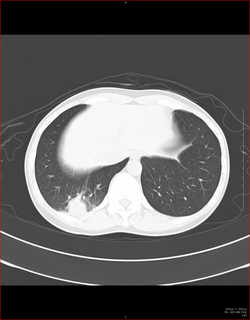

CTで見ると…

3Dだと、こうなります。

気管狭窄ですね。こういう所見もレントゲンで捉えることができるのです。